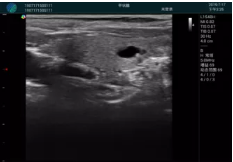

頸動脈血流充盈飽滿,無外溢